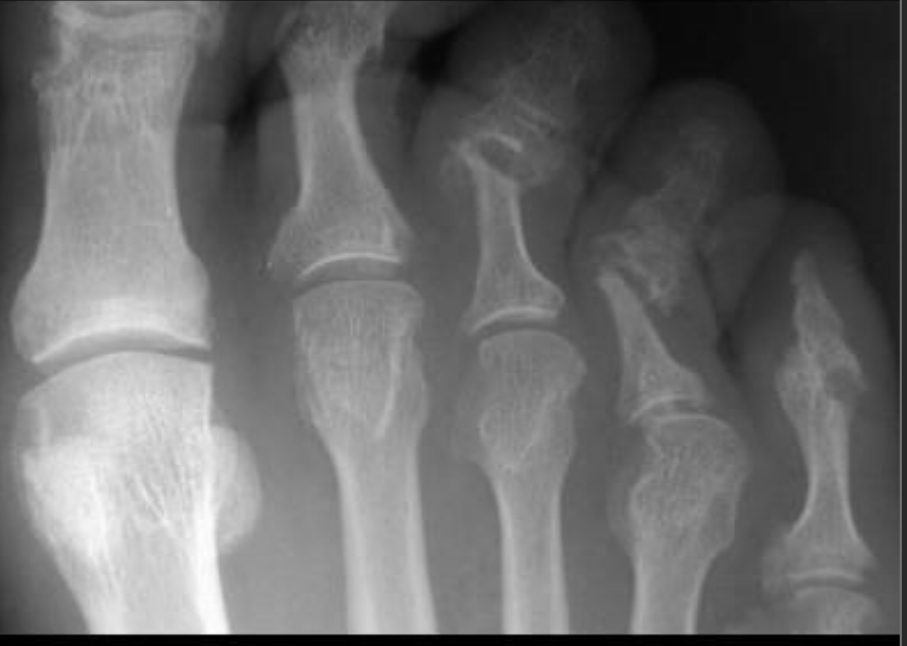

34M with forefoot pain

Psoriatic Arthritis

erosions in the metatarsophalangeal (MTP) and interphalangeal (IP) joints is nonspecific.

However, the florid periostitis strongly suggests either psoriatic arthritis or chronic reactive arthritis.